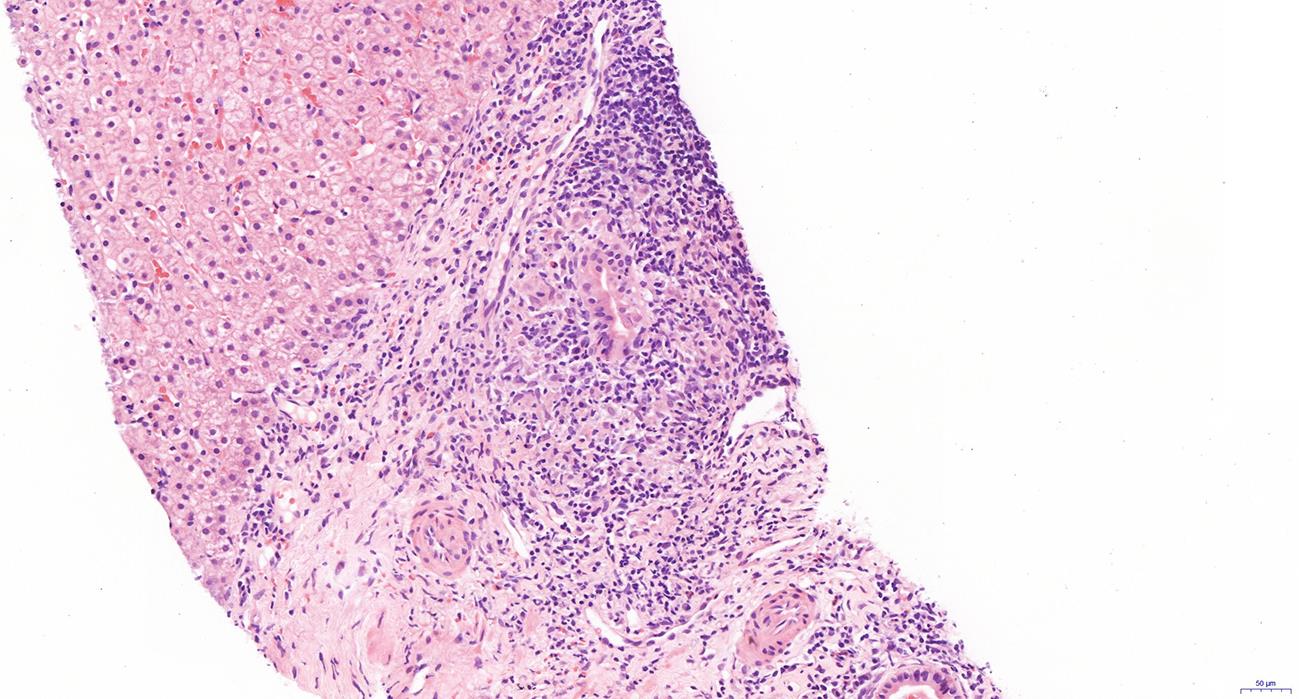

自身免疫性肝炎(AIH)是免疫介导的肝实质炎症性疾病,以高丙种球蛋白血症、自身抗体阳性和典型的肝组织学异常为特征。然而,AIH临床表现多样,缺乏特异性的血清学标志物,因此AIH的诊断困难,具有挑战性。虽然汇管区淋巴浆细胞浸润、界面性肝炎、淋巴细胞穿入现象和肝细胞玫瑰花结为AIH典型的组织学特征,但在AIH中尚可观察到其他的一些形态学改变,包括小叶中心性坏死、Kupffer细胞内透明小球等。所以没有一个单一的组织学特征可直接诊断AIH,需结合临床和实验室检查,并排除其他原因引起的肝脏疾病,方可做出正确的诊断。本文总结了AIH的组织学特征、不同的病理组织学谱、常见的临床问题、主要的鉴别诊断和最新进展。